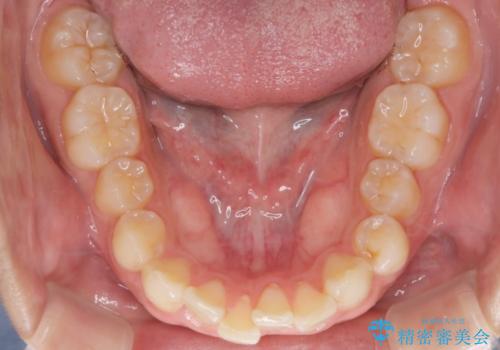

- 前歯のがたつきと口元を下げたいとのことで来院されました。

骨格的に左右差があるので正中を合わせることと抜歯矯正での口元改善は難しいことを説明させていただきました。

患者様に理解していただいた上で、インビザラインにてIPR(歯と歯の間を削る処置)を行いながら前歯のがたつきを整える治療計画を立てました。